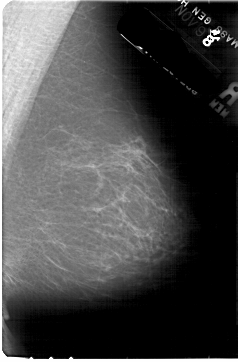

A_1872_1.RIGHT_MLO

RIGHT_CC LINES 5491 PIXELS_PER_LINE 3421 BITS_PER_PIXEL 12 RESOLUTION 43.5 NON_OVERLAY

RIGHT_MLO LINES 5416 PIXELS_PER_LINE 3556 BITS_PER_PIXEL 12 RESOLUTION 43.5 NON_OVERLAY